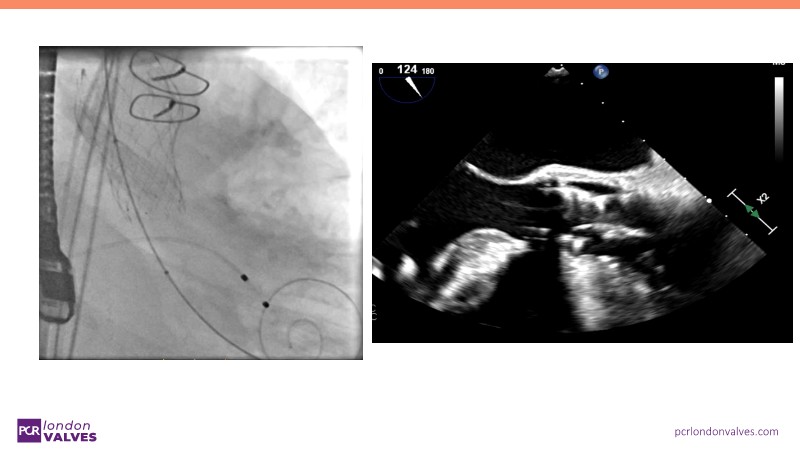

This session offers an in-depth review of complex TAVI cases, focusing on overcoming clinical challenges and achieving optimal outcomes with the Evolut FX+ device. Participants will learn about recent advances in TAVI indications for younger and asymptomatic patients, strategies for managing TAV in surgical aortic valve (SAV) patients including redo TAVI, and explore technological innovations designed to address complex anatomical scenarios.